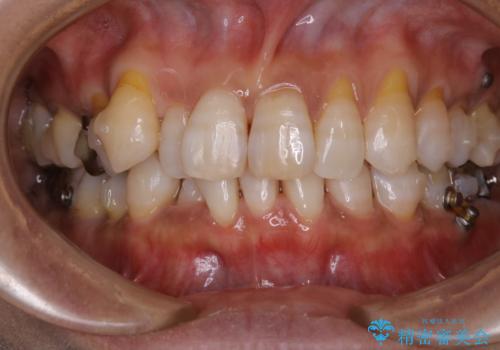

INVISALIGN治療中のPMTC

- INVISALIGN治療中に着色が気になり、クリーニング希望とのことで来院されました。PMTC30分コースを行いました。

インビザライン治療中には、歯の表面にアタッチメント(効率的に歯の移動をするもの)を設定します。そのため歯ブラシでは届きにくい細かい部分などに、歯石や着色がついてしまうことがあります。着色などを放置していると、着色なのか、虫歯なのかの判別もしずらく正確にお口の中の状態を診断できません。

矯正治療中も定期的に歯科医院にてPMTCを受けて、お口のケアを行うことをおすすめします。